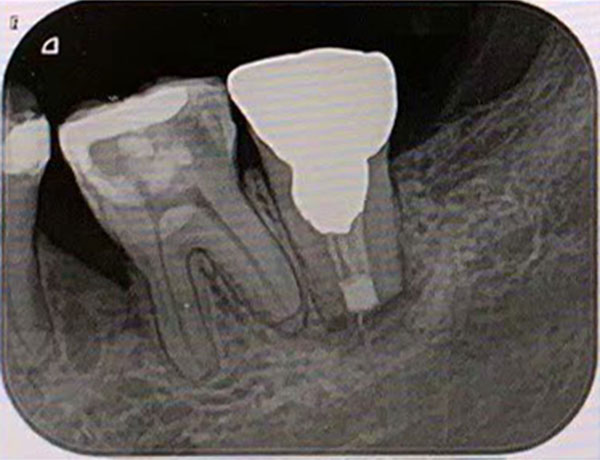

主訴: 噛むと痛い、左で食べれない。他の病院で神経が見つからない。根の先に病気がある。

通常だと手立てがなく、抜歯しかない歯も外科(根尖切除術)で治すことができます。

歯茎が腫れ、CT上では骨が大きくないことがわかります